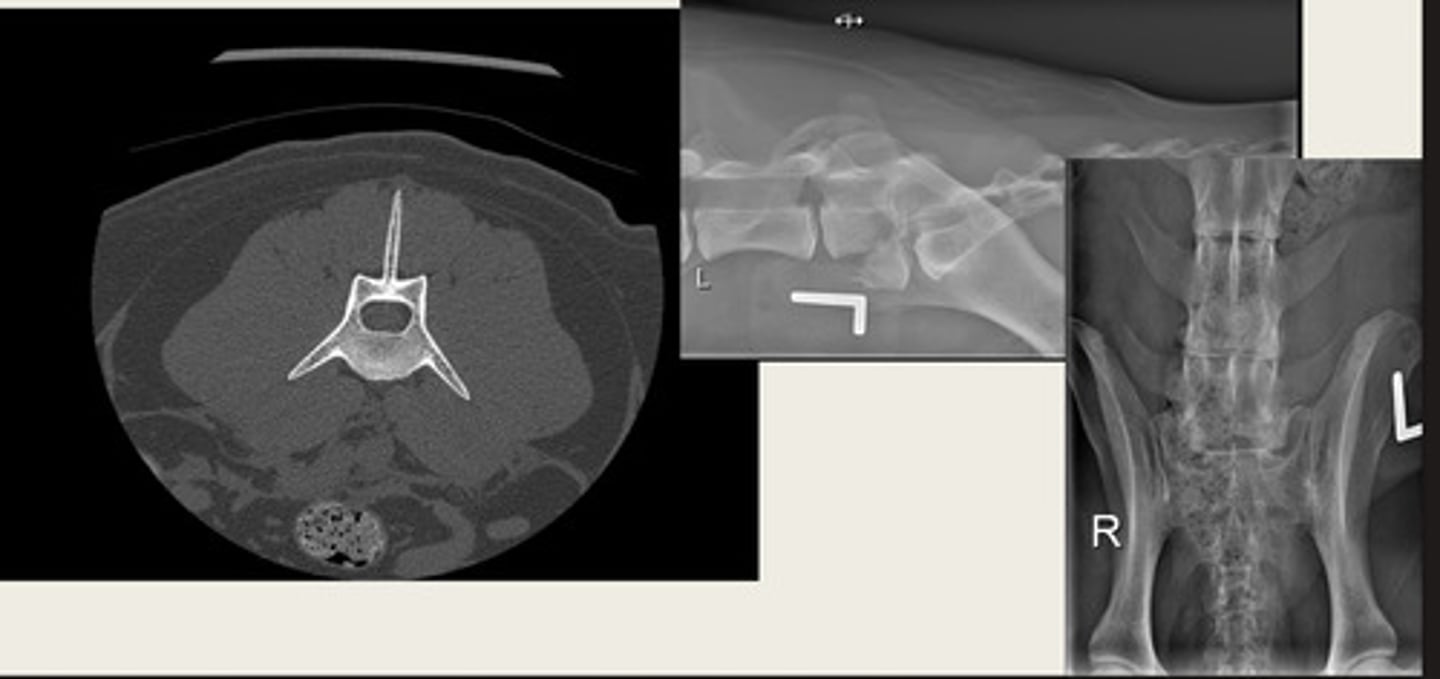

transverse

CT images are typically acquired in transverse/sagittal/dorsal?

left- bone window

right- tissue window

which CT window shows bone window or tissue window?

left- soft tissue window

right- bone window

ID the CT windows

which CT images are pre and post contrast? what type of window is being shown in both?

tissue density

what is this CT measuring?

CT volume rendering/3D reconstruction

what is the image on the left showing?